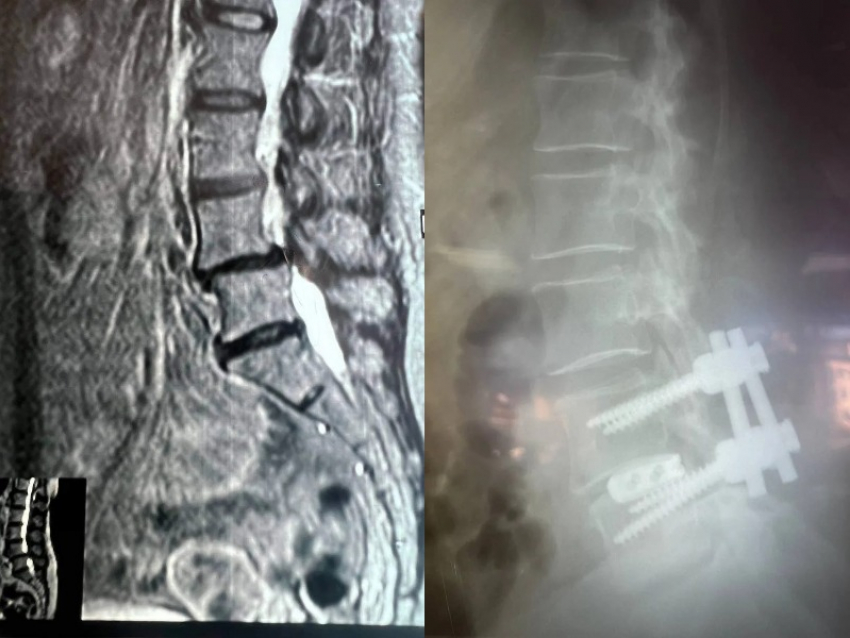

В начале марта в нейрохирургическое отделение стационара городской больницы №11 поступила женщина 1965 года рождения. Её беспокоили боли в пояснице и ногах, сами ноги немели при ходьбе, а ходить пешком было трудно.

Как рассказали в пресс-службе облздрава, после всех исследований врачи выявили у пациентки множество патологий, в частности поражение межпозвоночных дисков, сужение пространства позвоночного канала на уровне 4-5 позвонков поясничного отдела и другие.

В последние месяцы боль усиливалась, резко сократилась дистанция ходьбы. В ВГКБ №11 пациентке предложили декомпрессивно-стабилизирующую операцию на позвоночнике.

«Врачи «разжали» позвонки с двух сторон, удалили грыжу и диски поражённых частей заменили на импланты. С помощью оптического прибора, микрохирургической техники и инструментария врачи избавились от компрессии защитной оболочки спинного мозга и сегментарных нервов с двух сторон. Также женщине сместили в нужное место позвонок. Для стабилизации позвоночника, врачи установили конструкцию из четырёх титановых винтов и двух балок между ними», – отметили в Минздраве.

Там добавили, что послеоперационный период прошел без осложнений. На следующий день пациентка болей в ногах уже не чувствовала, ей разрешили вставать и ходить. За неделю восстановились функции нервов и нормализовалась походка. На 8-й день после операции женщину выписали.